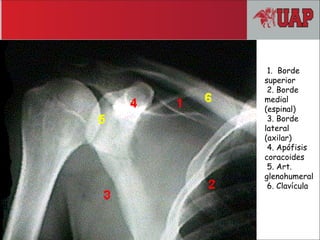

1. Borde

superior

2. Borde

medial

(espinal)

3. Borde

lateral

(axilar)

4. Apófisis

coracoides

5. Art.

glenohumeral

6. Clavícula

1. Borde superior 2. Borde medial (espinal) 3.Borde lateral (axilar) 4. Apófisis coracoides 5. Art. glenohumeral 6. Clavícula